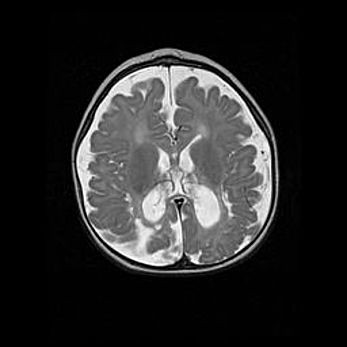

Лейкомаляция с кистозно-глиозной дегенерацией головного мозга.

Возраст: 2 месяца 25 дней

Вес: 6400 г

Окружность головы: 40 см

Срок гестации: 41 неделя

Лейкомаляцию относят к ишемически-гипоксическим повреждениям головного мозга, диагностируемым у новорожденных. При лейкомаляции в головном мозге обнаруживают очаги некроза, возникшие после тяжелой гипоксии и нарушения кровотока. В процессе морфогенеза очаги проходят три стадии: 1) развития некроза, 2) резорбции и 3) формирования глиозного рубца или кисты. Перивентрикулярная лейкомаляция (ПЛ) встречается примерно в 12% случаев среди новорожденных, обычно – у недоношенных детей, причем, частота ее зависит от массы, с которой младенец появился на свет. Наибольшее число малышей страдает лейкомаляцией, если масса при рождении 1500-2500 г.